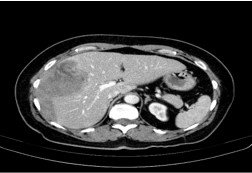

Simple Hepatic Cyst

–Congenital benign lesion, often incidental

–Water-density lesion on CT

–No enhancement in any contrast phase

–MRI: T1 hypointense, T2 very hyperintense

–Thin wall, no septa or mural nodules

–No treatment if asymptomatic